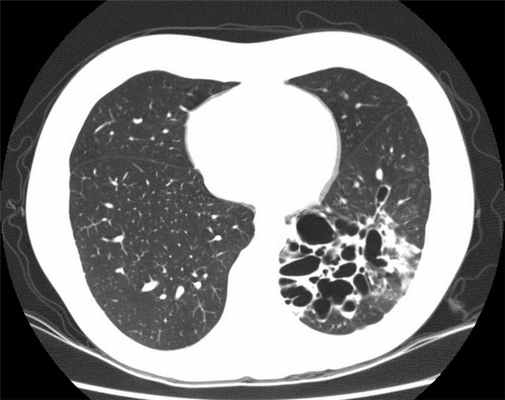

В окончательной постановке диагноза важнейшее значение имеют лучевые методы диагностики. При рентгенографии выявляются тяжистость, ячеистость, кистовидные изменения лёгочного рисунка, уменьшение объёмов отдельных зон лёгкого, эмфизематозность (воздушность) в смежных участках лёгкого. В настоящее время основным диагностическим исследованием является компьютерная томография (КТ, МСКТ). Это связано с большой информативностью метода при неинвазивном и безопасном характере его применения.

- КТ (компьютерная томография): это исследование необходимо для диагностики бронхоэктазов. При этом ваше тело подвергается рентгеновскому облучению под разными углами с последующим компьютерным составлением изображения с высокой точностью.

Поставить точный диагноз помогает компьютерная томография с высоким разрешением. Обычная флюорография нужной информации о характере, локализации и развитии БЭБ не даст. Кроме этого специалисты используют другие аппаратные и лабораторные методы, дающие подробные сведения о течении заболевания. Это:

Достоверный диагноз бронхоэктатической болезни или бронхоэктазов ставится только после проведения компьютерной томографии органов грудной клетки в режиме высокого разрешения